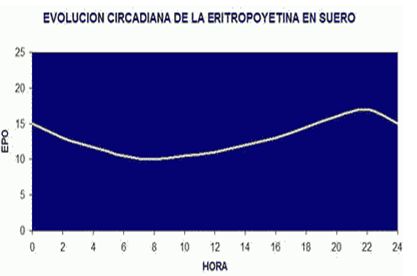

La EPO presenta un ciclo circadiano, y los valores máximos suelen darse entre las 16:00 y las 22:00 de la tarde-noche, y los valores mínimos a las primeras horas de la mañana.

Figura 4. Ritmo circadiano de la eritropoyetina (www.biolaster.com)